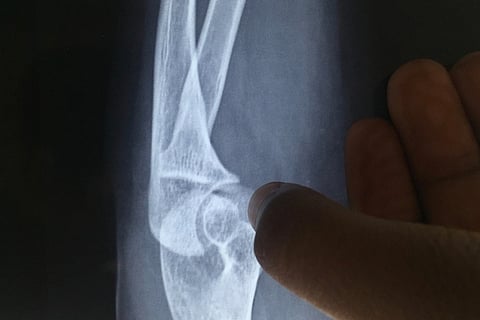

Osteoporosis is a term which literally means “porous” bone. As the name suggests, it is a result of loss of bone density as a result of which the bones become brittle and fragile, putting them at risk of fracturing easily. Many women may develop osteoporosis around menopause, for which certain precautionary measures should be taken.

What can happen if osteoporosis goes undetected? According to Dr Krishnan M, an orthopedician from Bengaluru, someone with osteoporosis is at risk of developing fractures due to physical injuries. Areas such as the spine or the head of the thigh bone (femur) are the areas that are most commonly prone to fractures.